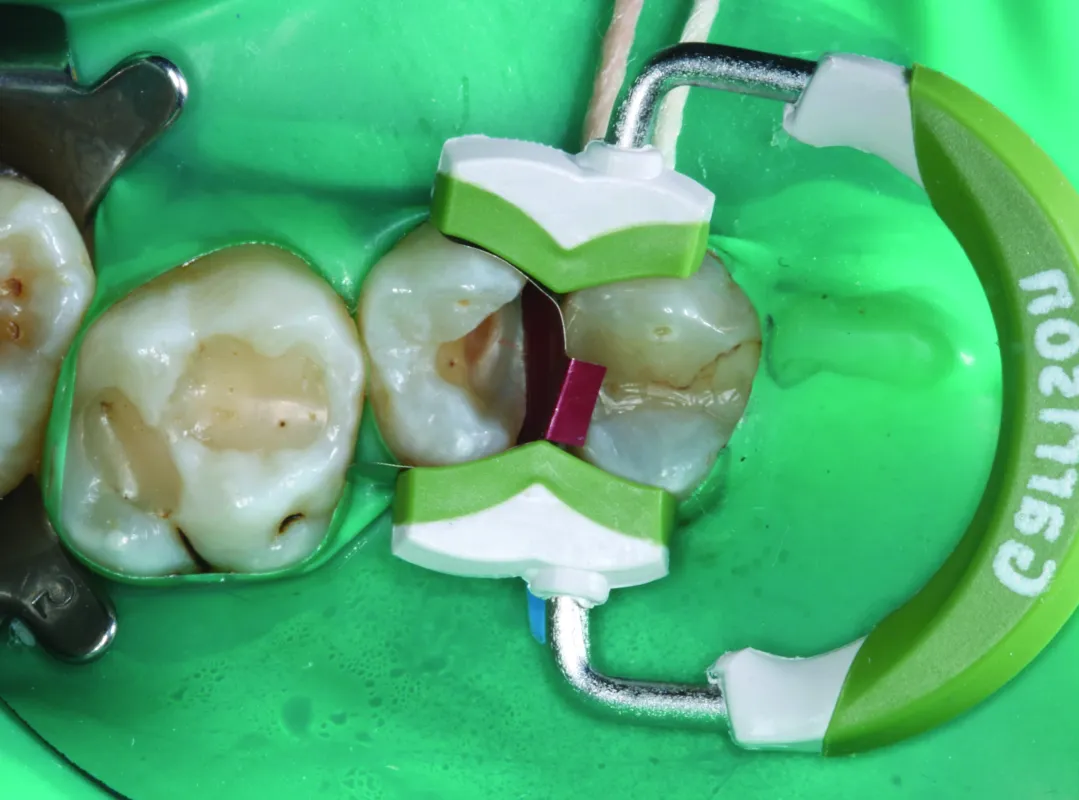

Modern sectional matrices, interproximal wedges and ring systems like the Garrison sectional matrix system make the procedures more predictable and allow dental practitioners to restore such cavities easily.

The presented case is removal of the interproximal caries with deep cervical margin and wide buccal and palatal extensions. After the cavity preparation and isolation with the rubber dam, Garrison matrix with extension, Blue (small) wedge and Wide Prep (green) ring were placed. The wide extensions of the ring allow to restore adequate buccal and palatal contours of the tooth. The sectional matrix is easily shaped to restore proper anatomy and tight contacts. The rest of the cavity is filled with respect of the simplified tooth anatomy. Rough polishing and contouring were done under the rubber dam isolation. After the removal of the rubber dam the procedure ends with fine polishing and occlusal corrections.